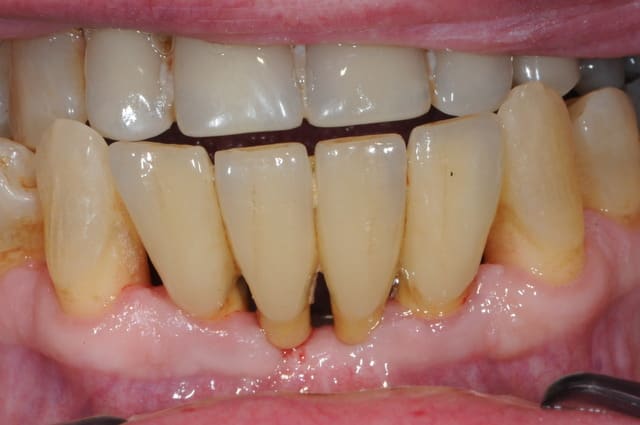

dentiste57

01/07/2009 à 22h45

hi hi

j'en ai un du même genre...

faut quand même que je lui dise de brosser un peu plus.